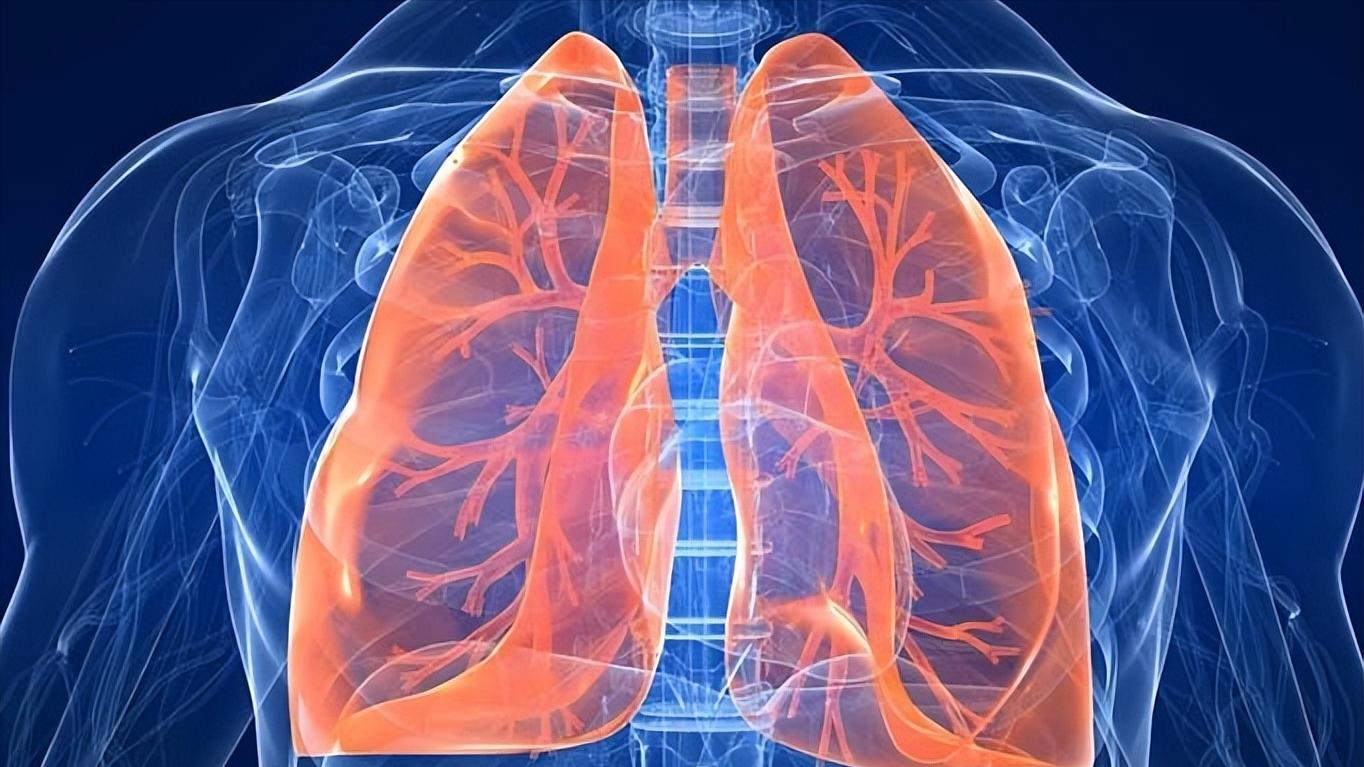

肺,属于呼吸系统,不仅是人体重要的呼吸器官,也是人体造血系器官,左右两边各一个。肺的质地松软而富有弹性,像我们生活中经常看到的气球一样。肺里面除了有肺泡之外,还有气管、支气管、淋巴管,以及动、静脉血管等组织结构。这些组织结构非常密集,从两肺的肺门开始向边缘不断延伸,越靠近边缘,这些组织就会越细。

通俗点讲,我们的肺像一棵倒置的大树,肺部的气管、支气管、动、静脉血管、淋巴管等组织就像大树的主干和树枝,大树的树枝越往上延伸,就会越细,肺部组织也是如此。

肺纹理是放射科的一个专业术语,是指胸部影像检查时所看到的从肺门向肺周围延伸的放射条状阴影。这种呈放射条状,像大树一样的阴影主要由我们刚刚说的肺动脉、肺静脉、支气管及淋巴管这些组织组成的。